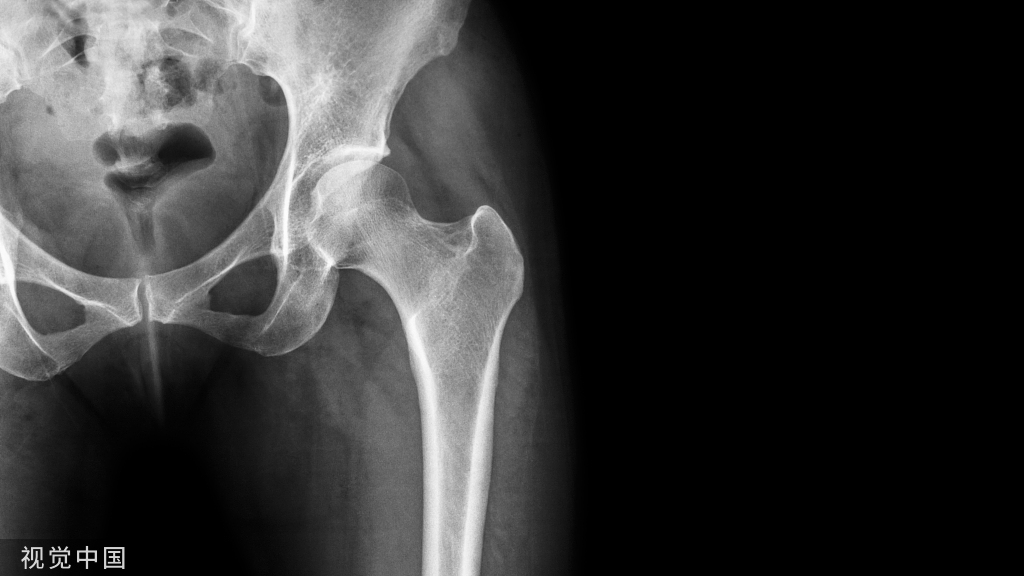

滑膜囊为一密闭的结缔组织扁囊,有的与关节腔相通,有的则独立存在。大小数mm至数cm。多存在于皮肤,肌肉,肌腱,韧带与骨面之间。囊腔内含少量滑液,其作用为增加润滑,减少摩擦,促进运动的灵活性。

在外伤或长期的磨损的影响下,可发生滑膜炎或滑膜囊肿。有些滑膜囊与关节交通,关节感染时,关节腔内侧脓液可进入囊内,蔓延成为关节旁脓肿。